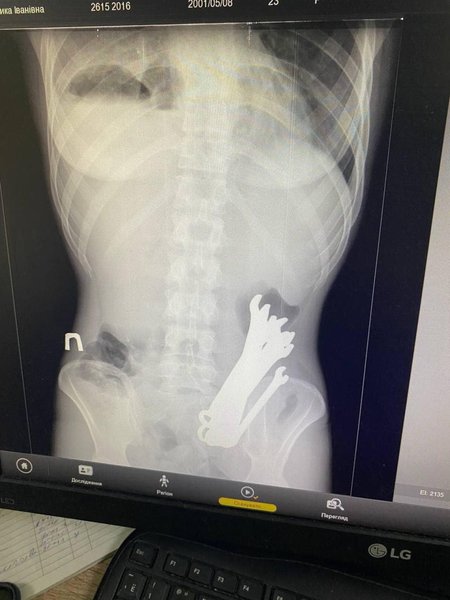

В Черкассах медики спасали мужчину, который попал в больницу в тяжелом состоянии. Рентген показал, что в желудке пациента посторонние железные предметы. Об этом сообщили в отделении торакальной хирургии Черкасской областной больницы.

Медики больницы провели операционное вмешательство и достали из тела пациента 6 гаечных ключей. После трех недель лечения его выписали из медучреждения. Каким образом инструменты оказались в желудке мужчины — не сообщается.